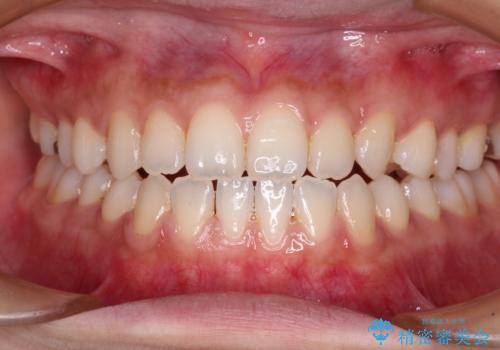

舌突出癖で口元が開いてしまう 舌トレーニングを行ったインビザライン矯正

- 前歯の上下スペースと前歯の隙間を気にして来院された患者様です。

インビザラインにより上下の前歯の隙間を閉じていくこととしました。

上下の隙間に舌が入り込むことが、すきっ歯やオープンバイトの原因であったため、舌の筋肉のトレーニングも並行して行い、後戻りの抑制を図りました。